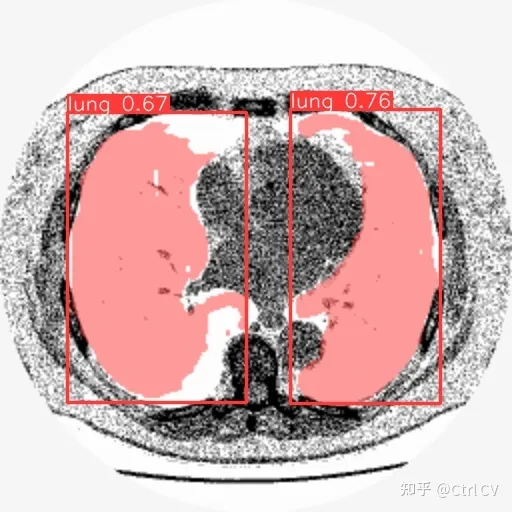

一、肺部CT图像数据

mask

在测试数据上检查结果: